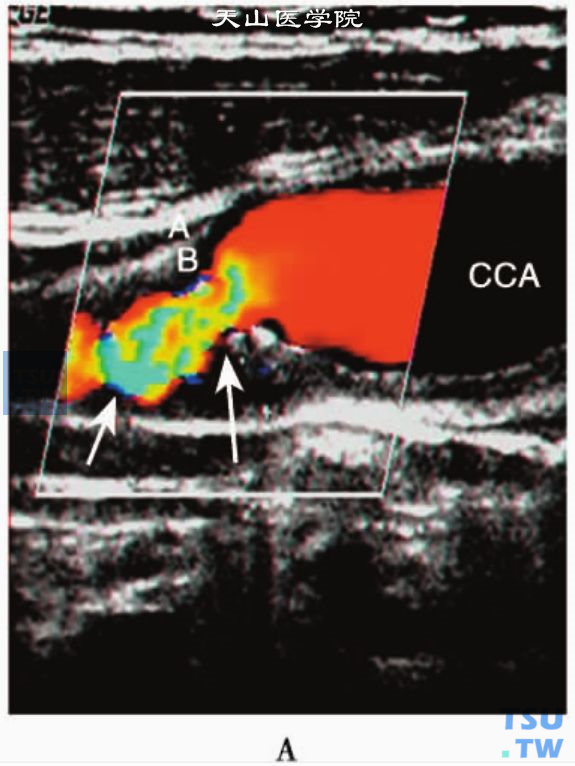

1超声检查仪器、方法和内容检查颈动脉应采用高分辨率彩色多普勒超声仪,选用线阵探头,频率一般为5~10MHz。通常沿颈动脉血管长轴纵向扫查血管,必要时辅以血管横断扫查。受检者取仰